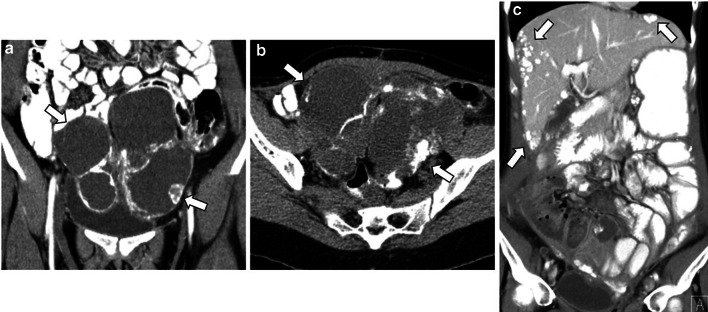

Fig. 7.

Three cases demonstrating the main radiological features of SBT, LGST and HGST. Sagittal T2-weighted image (a) and axial fat saturation T1-weighted image after gadolinium administration (d) reveal a right unilocular cystic tumour with well-defined margins and small enhancing papillary projections (arrows). Histologic examination was compatible with SBT. Axial T2–weighted MR image (b) and axial unenhanced CT image (e) show a bilateral mixed LGST with solid parietal components (arrows) and calcified psammoma bodies (arrowheads). Sagittal and coronal T2-weighted images (c and f) demonstrate a bilateral mixed HGST with irregular contours and exuberant solid components (arrows). Several abdominal (not shown) and pelvic peritoneal metastases (arrowheads) and ascites (stars) were noted

LGSC is characterised by delayed metastatic dissemination, usually through nodular peritoneal metastases throughout the abdomen [2] (Figs. 4, 6).

The classic psammoma bodies, calcified extracellular bodies, can occur within serous tumours or peritoneal metastases, especially in LGSCs (90% of cases) [4, 10–12, 17] (Figs. 5, 6, 7). These tiny calcifications are detected in 30% of tumours at histology but only in 12% of cases at CT [2]. Several authors endorse the use of non-contrast CT and intestinal opacification with water to differentiate tiny calcifications from intestinal loops, particularly in LGSC [1, 13].

Peritoneal metastases, nodal calcifications, papillary projections in cystic lesions, and the presence of necrosis are findings that suggest malignancy and help to distinguish malignant serous tumours from benign lesions [1, 4, 17]. Ascites is also rarely identified in LGSC, whereas HGSC typically presents abundant ascites and diffuse peritoneal metastases (Figs. 6, 7) [1, 4, 8].